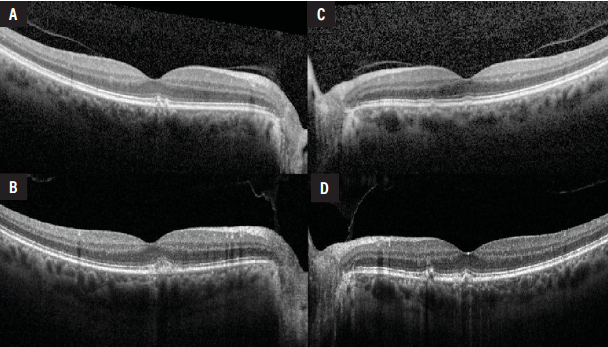

Fundus autofluorescence demonstrated hyper- and hypoautofluorescent changes throughout the posterior pole and mid-periphery (Figure 1C and 1D). Optical coherence tomography was notable for scattered sub-RPE deposits in both eyes (Figure 2). On comparison with imaging obtained four years prior to presentation to our service, there was mild blunting of the foveal contour in the right eye and progression of the sub-RPE deposits in both eyes (Figure 2B and 2D). Neither eye developed cystoid macular edema, subretinal fluid or hemorrhage.

| Figure 2. Optical coherence tomography of the right and left eyes on initial evaluation when she was first diagnosed with AMD (A, B), compared to the first presentation to our service four years later (C, D). There are sub-RPE deposits in both eyes with evidence of progression over time. In the right eye there is mild blunting of the foveal contour (C). There is no cystoid macular edema, subretinal fluid or hemorrhage in either eye. |